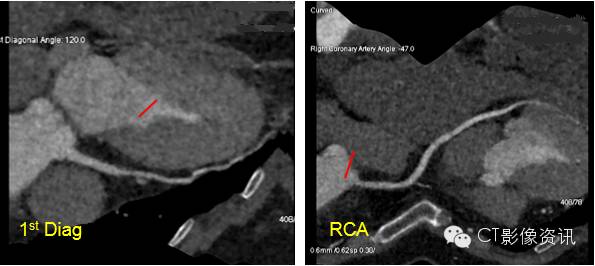

Case 2 女性,53岁,胸闷、心悸月余,高心率:90~104bpm

扫描协议 探测器宽度:120mm, Axial; 管电压和管电流:80kV, Smart mA; 旋转速度:0.28s/rot ;迭代:ASiR-V 60%;体重指数:25.14; 对比剂:270mgI/ml, 35ml, 4.5ml/s; 扫描剂量 :0.37mSv。

CCTA所见 1st Diag,RCA起始非钙化斑块,管腔轻度狭窄。

点评 Revolution CT拥有29ms的时间分辨率,配合Auto-Gating技术,实现任意心率/律下ONE BEAT成像,不仅明显降低射线剂量,还可以采用更低的造影剂用量,且得到显示清晰的冠脉图像质量,使低/超低剂量冠脉扫描成为常规临床应用。